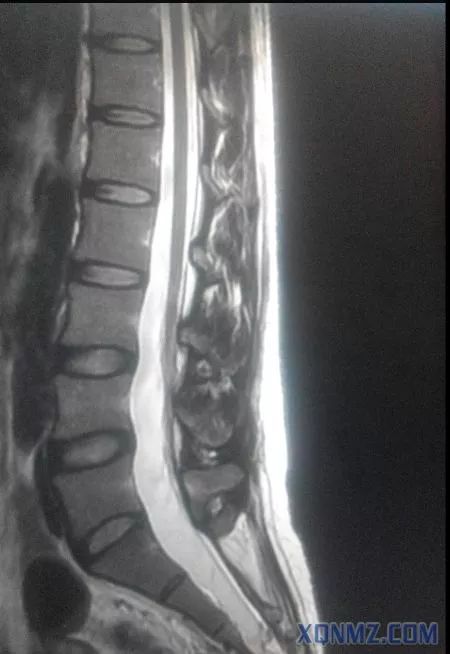

下面是我工作中在影像科学习时发现了一例中年女患,脊髓变异,终止于L3-4,而不是L1下缘,此患者要是做腰麻后果不堪设想,相信大家做腰麻时不可能所有的患者都术前做磁共振检查吧。